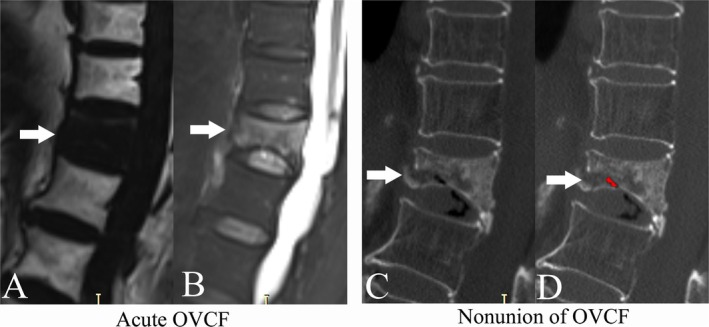

Objective: Increased marrow fat fraction (MFF) of vertebrae was detected in patients with osteoporosis. However, MFF of the fractured vertebrae decreased significantly following the fracture. The aim of this study was to assess the predictive value of fractured vertebrae MFF quantified on T2-weighted Dixon sequences for the prediction of nonunion risk of acute OVCF.

Materials and methods: Medical records of 39 patients with OVCF, including a total of 60 fractured vertebrae, were reviewed retrospectively. Fractured vertebrae in the acute phase were grouped into the nonunion group (20 vertebrae) and the union group (40 vertebrae), based on the OVCF prognosis confirmed by computer tomography (CT). MFF of the fractured vertebrae was quantitatively assessed with the software Matlab on T2-weighted Dixon sequences. Interclass correlation coefficients (ICC) were analyzed to assess the repeatability of MFF measurement. Binary logistic regression analysis was performed to determine the relative contribution of the MFF for predicting the prognosis of OVCF. Receiver operating characteristic (ROC) curve analysis was performed to determine the diagnostic performance of MFF.

Results: The ICC indicated that the repeatability of MFF measurement was excellent (all p < 0.001). The MFF (42.25% ± 26.61%) decreased significantly compared to the value before OVCF (79.84% ± 9.65%) (p < 0.001). The MFF of the fractured vertebrae was lower in the nonunion group (16.40% ± 15.65%) than in the union group (55.18% ± 20.93%) (p < 0.001). Binary logistic regression analysis indicated that MFF of fractured vertebrae could independently predict the prognosis of acute OVCF (p < 0.001). ROC analysis indicated the area under the curve was 0.928 (95% CI, 0.831-0.979, p < 0.0001).

Conclusions: The MFF quantified on T2-weighted Dixon sequences was a useful marker for assessing the nonunion risk of acute OVCF. The fractured vertebra with low MFF should be carefully monitored for nonunion.